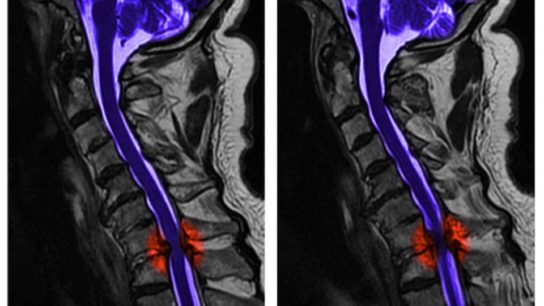

Researchers observed the trajectories of tissue-specific spinal cord neurodegeneration above and below traumatic and nontraumatic spinal cord injuries.